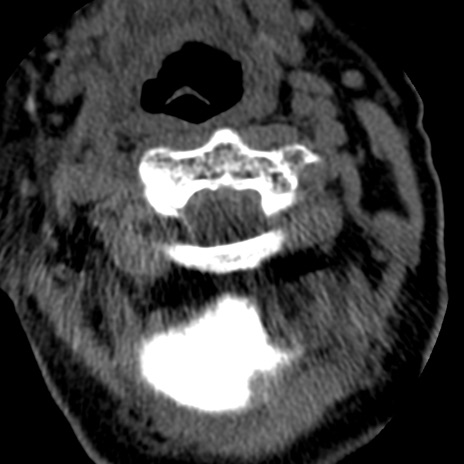

症例50 頚椎CT(横断像)

頚椎CT

矢状断像